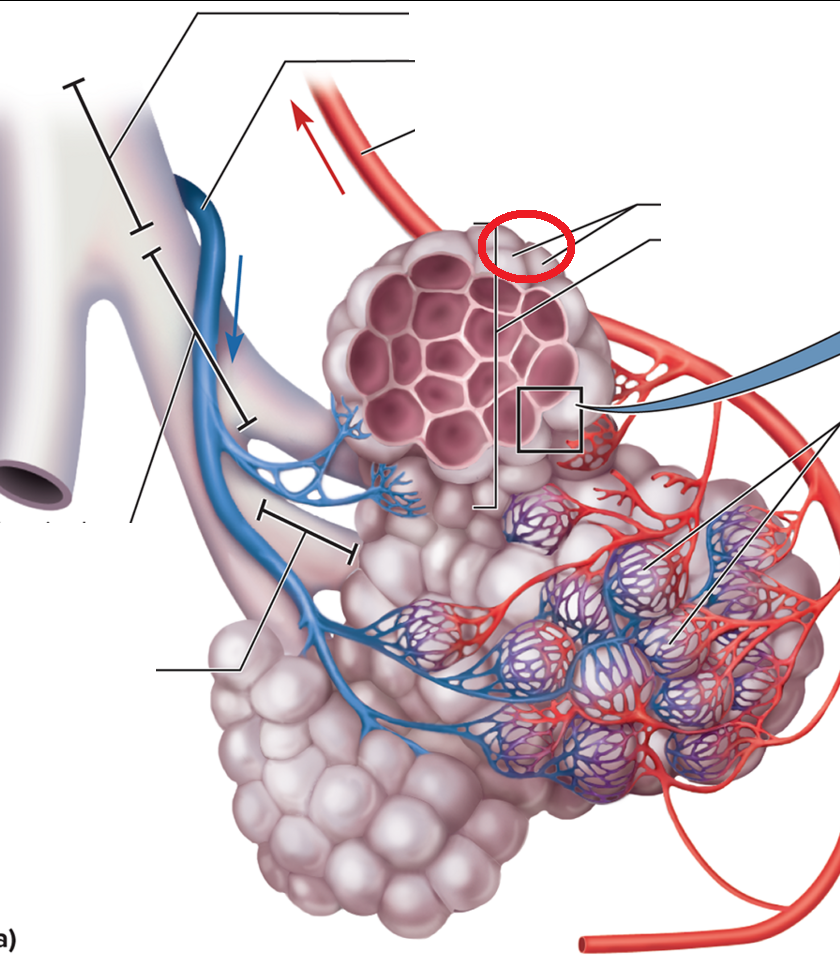

Trachea and Bronchial Tree

resp bronchiole

Alveolar duct BT

Alveolar sac BT

Alveolus BT